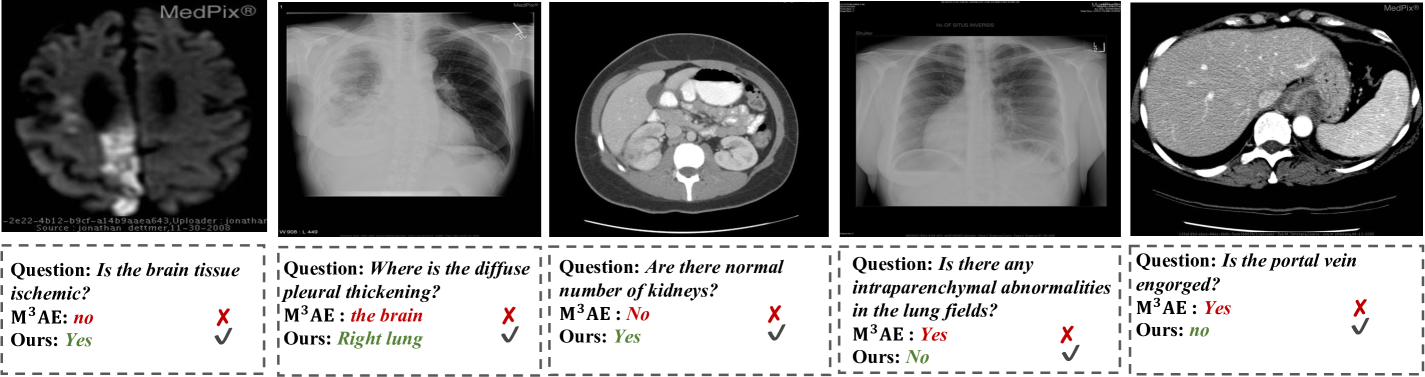

Figure 6: Visualization of medical VQA comparison on VQA-RAD dataset. Our UMD framework is capable of providing more accurate answers to medical questions of different difficulties.

4.5 Qualitative Analysis

For a qualitative comparison, we further present 5555 VQA test samples from the VQA-RAD dataset to provide predicted results of M3AEsuperscriptM3AE\rm{M^{3}AE}roman_M start_POSTSUPERSCRIPT 3 end_POSTSUPERSCRIPT roman_AE and our UMD framework, as shown in Fig. 6. Compared with M3AEsuperscriptM3AE\rm{M^{3}AE}roman_M start_POSTSUPERSCRIPT 3 end_POSTSUPERSCRIPT roman_AE, UMD can understand diagnosis-related information better and predict more accurate answers, which can benefit clinical diagnosis more effectively.